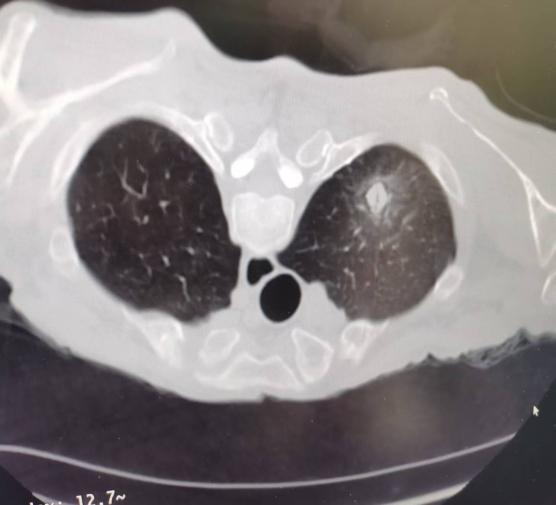

術(shù)前

大爺消化系統(tǒng)疾患就診于我院,在后續(xù)進一步檢查中,發(fā)現(xiàn)肺部存在高危結(jié)節(jié),考慮為早期肺癌。由于患者高齡,心肺功能,且合并多種慢性基礎(chǔ)疾病,傳統(tǒng)手術(shù)創(chuàng)傷大、風(fēng)險高使家屬和患者一度束手無策,治療陷入困境。經(jīng)我院腫瘤科團隊綜合評估患者身體狀況、腫瘤位置及大小,最終確定采用CT引導(dǎo)下肺結(jié)節(jié)活檢+同步射頻消融的個體化治療方案。